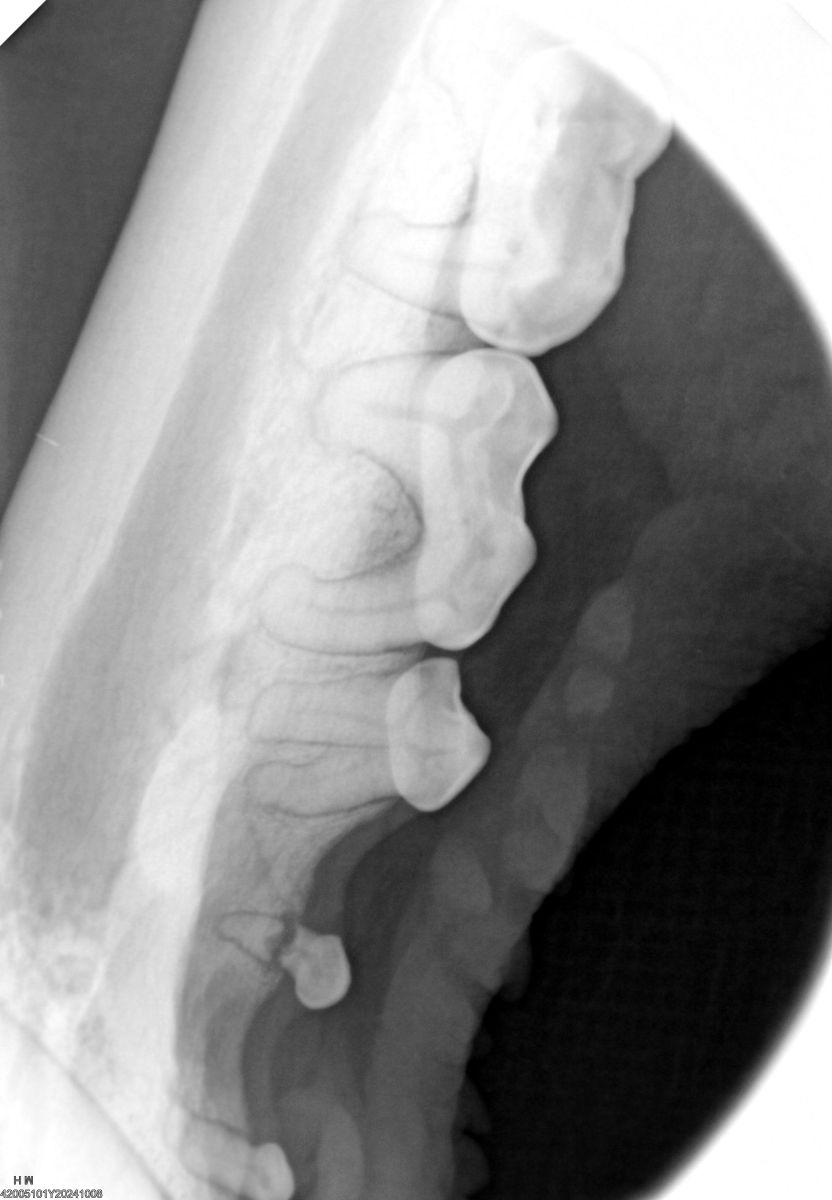

Purchase of an X-ray Machine and Generator – This purchase reduces stress for our animals and human caretakers by allowing veterinary staff to x-ray our residents on site. It also contributes to faster diagnoses and saves money. (See Bear Olive's mouth x-ray at left, where we discovered a broken tooth and extracted it, resulting in a happy, healthy bear.)